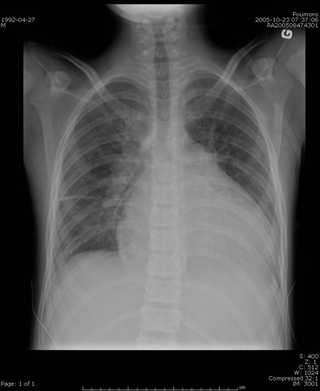

La cardiomégalie est une augmentation anormale de la taille du cœur. Elle peut être dépistée par une radiographie thoracique de face, en position debout, montrant un index cardiothoracique supérieur à 0,5 ou 0,55. Cet index est égal au rapport entre le plus grand diamètre horizontal du cœur et le plus grand diamètre horizontal du thorax, mesurés sur une radiographie thoracique conventionnelle.

Un « gros cœur » peut être du, soit à une augmentation d'une ou plusieurs cavités cardiaques, par exemple dans le cadre d'une cardiomyopathie dilatée, soit à un épaississement important des parois des ventricules cardiaques (hypertrophie ventriculaire gauche dans le cadre d'une cardiomyopathie hypertrophique). Il peut également parfois témoigner d'un épanchement péricardique. Ces différents diagnostics sont tranchés par une échocardiographie.